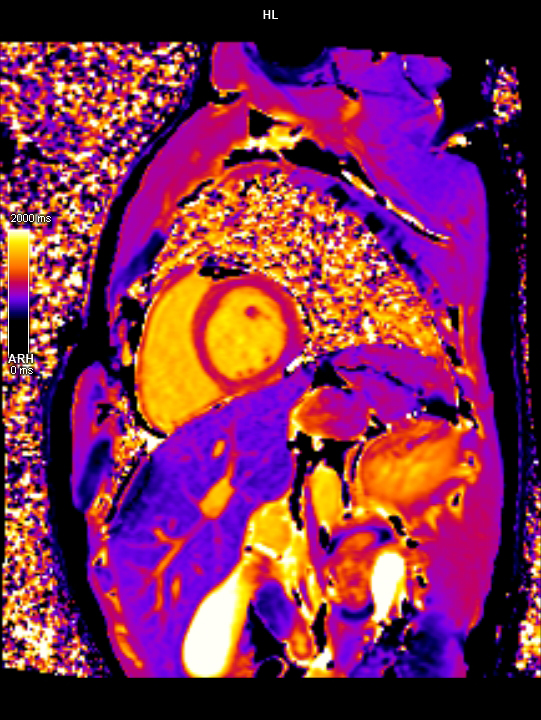

• 3 TESLA MR ÇEKİM GÖRÜNTÜLERİ

3 Tesla MR Çekim Görüntüleri

• 3 Tesla MR Çekim Görüntüleri